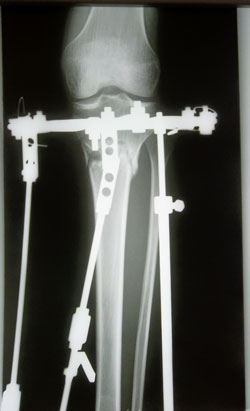

Дата операции 29.10.2013г.

Дата снятия аппаратов (с правой ноги) 07.02.2014г.

Дата снятия аппаратов (с левой ноги) 14.02.2014г.

Срок лечения 105 дней.